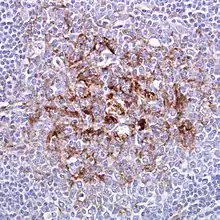

Biopsi af tonsilvæv ramt af vCJD. Immunhistokemisk farvet for PrP. Ekstracellulær ophobning samt ophobning uden for centralnervesystemet er patognonomisk for vCJD.

Diagnosen kan stilles definitivt på baggrund af nøje bestemte kriterier for hver enkelt af de forskellige typer af CJD. Præparatet vil farves immunhistokemisk for PrPSc. Kriterierne bygger på forskelle mellem typerne, herunder:

• Fordelingen af PrPSc i forskellige dele af hjernen

• Om PrPSc forekommer ekstracellulært

• Fordelingen af spongiform degeneration i forskellige dele af hjernen